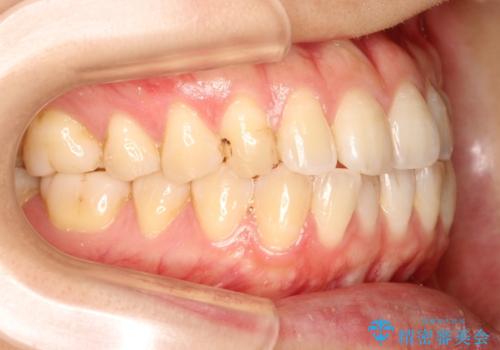

初診時の歯並びの状態としては、上下ともに前歯部に限局した軽度ののがたつき(叢生)がある状態でした。

主に歯列弓の拡大とディスキング(歯と歯の間に隙間を作る処置)を行い叢生を改善しました。

見た目、嚙み合わせ及び、治療期間や施術内容に大変ご満足いただきました。